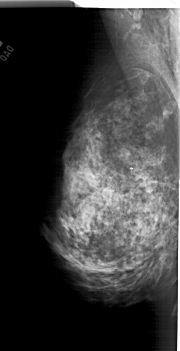

A_1762_1.LEFT_MLO

LEFT_MLO LINES 6316 PIXELS_PER_LINE 3226 BITS_PER_PIXEL 12 RESOLUTION 43.5 NON_OVERLAY